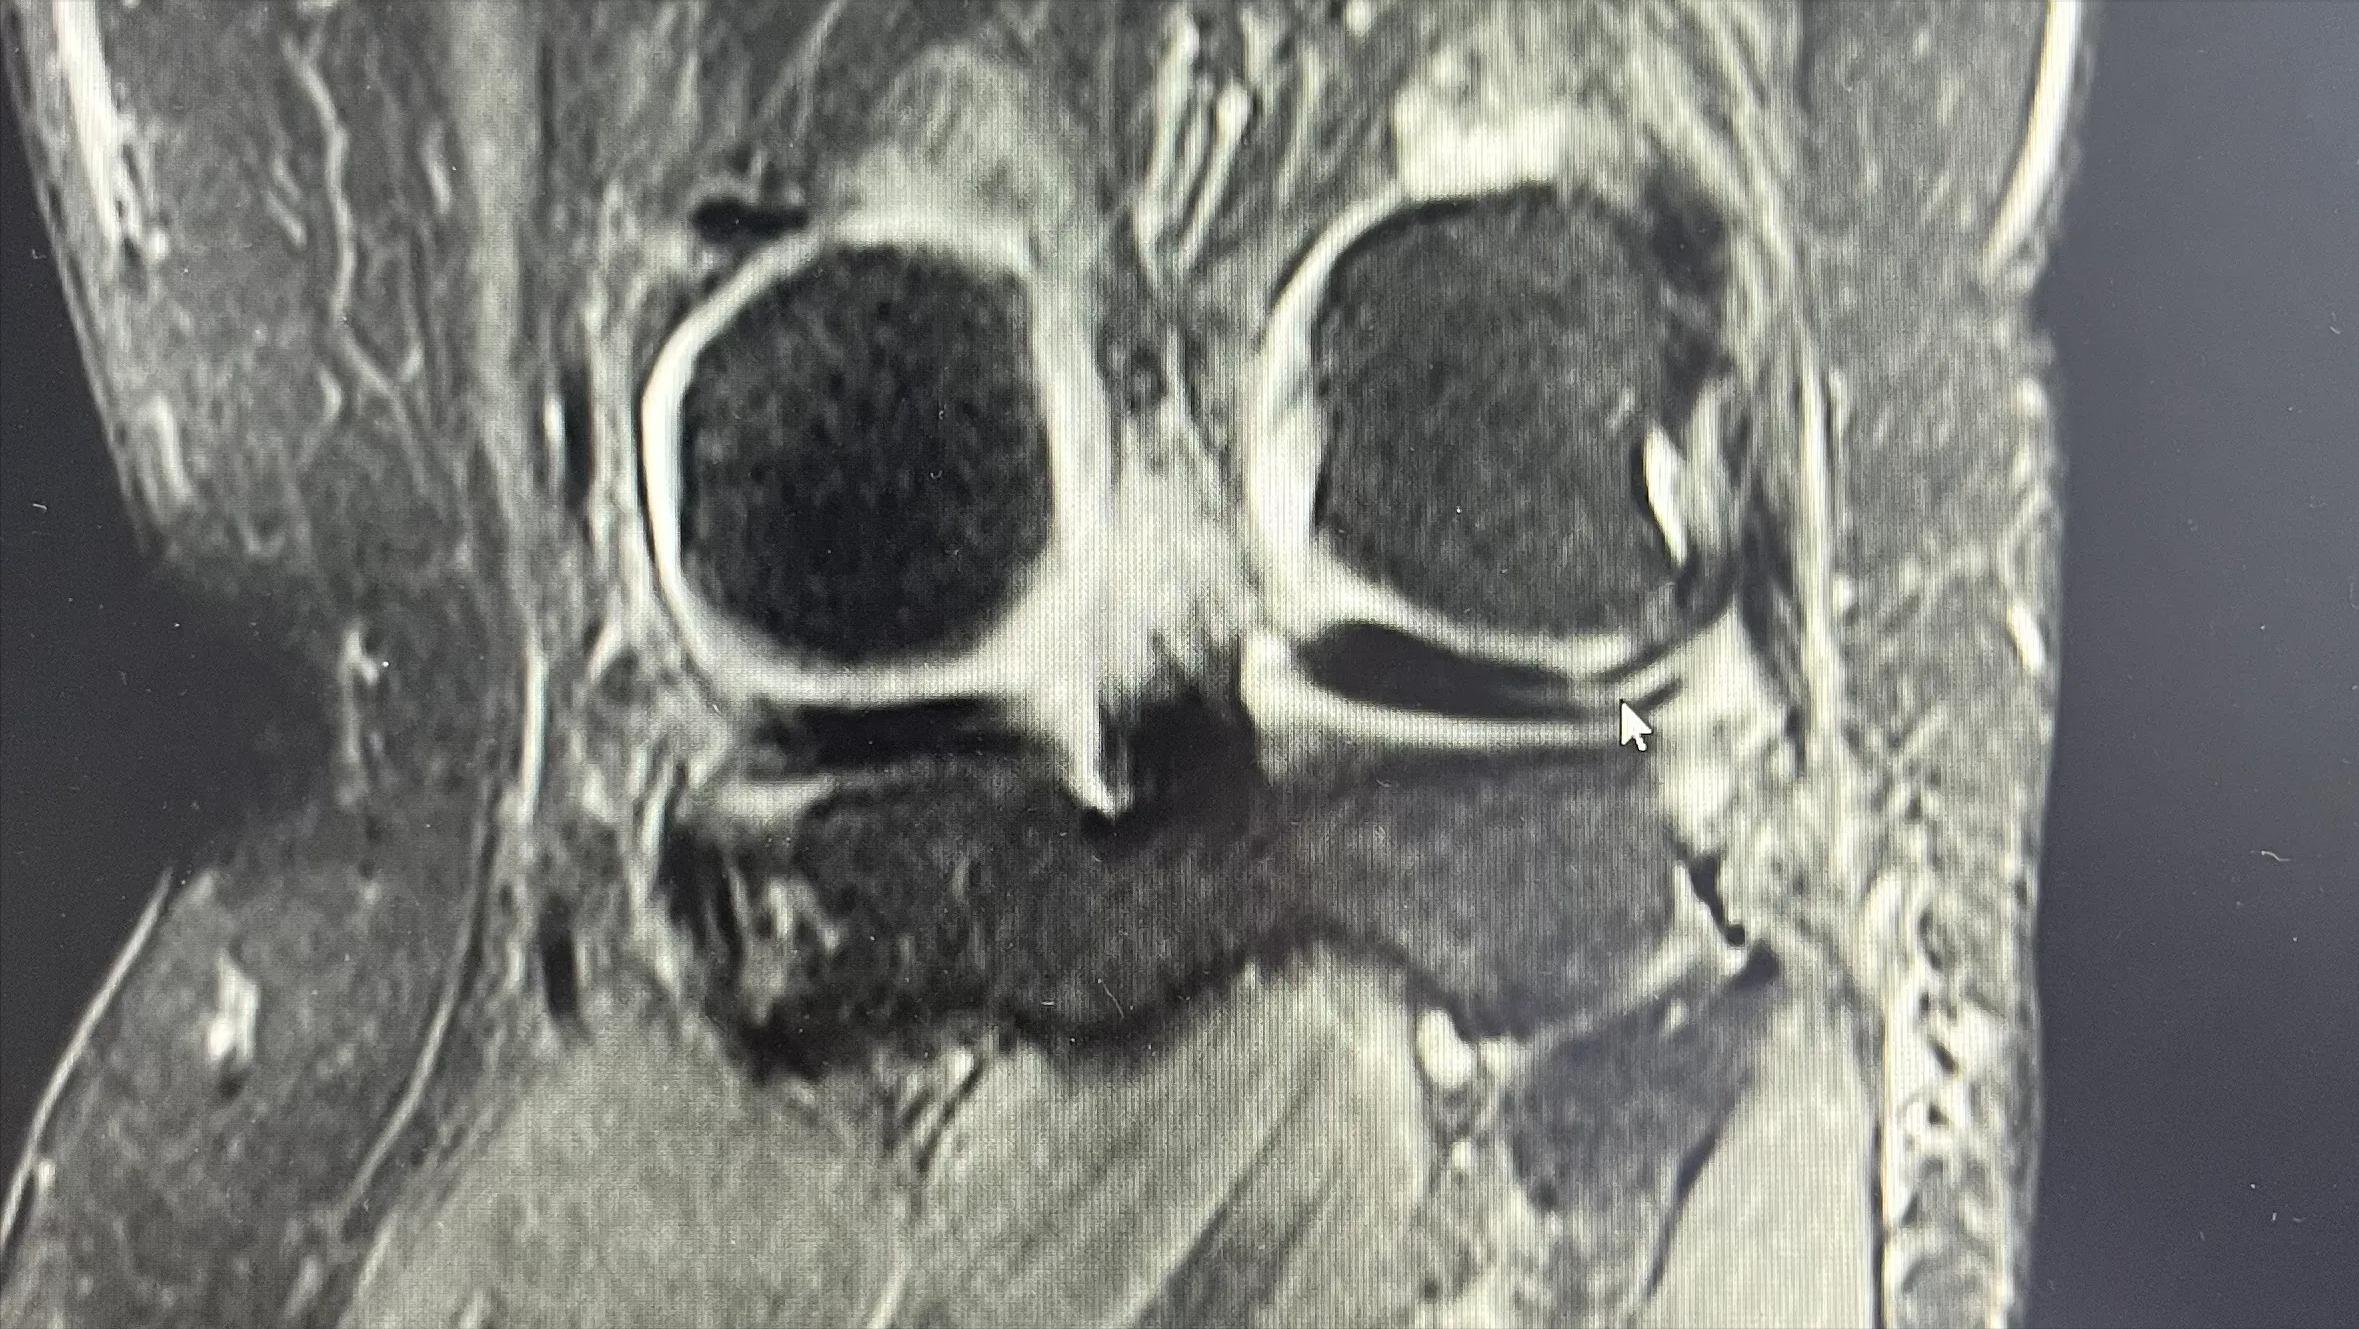

2022.1.20磁共振报告

半月板的轻微损伤要注意什么,半月板损伤两年多了最好的方法

首次磁共振检查光标处显示半月板三度损伤